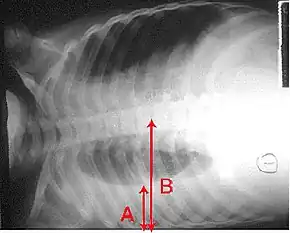

The World Health Organization has defined pneumonia in children clinically based on either a cough or difficulty breathing and a rapid respiratory rate, chest indrawing, or a decreased level of consciousness.[56] A rapid respiratory rate is defined as greater than 60 breaths per minute in children under 2 months old, greater than 50 breaths per minute in children 2 months to 1 year old, or greater than 40 breaths per minute in children 1 to 5 years old.[56] In children, low oxygen levels and lower chest indrawing are more sensitive than hearing chest crackles with a stethoscope or increased respiratory rate.[57] Grunting and nasal flaring may be other useful signs in children less than five years old.[58] Lack of wheezing is an indicator of Mycoplasma pneumoniae in children with pneumonia, but as an indicator it is not accurate enough to decide whether or not macrolide treatment should be used.[59] The presence of chest pain in children with pneumonia doubles the probability of Mycoplasma pneumoniae.[59]